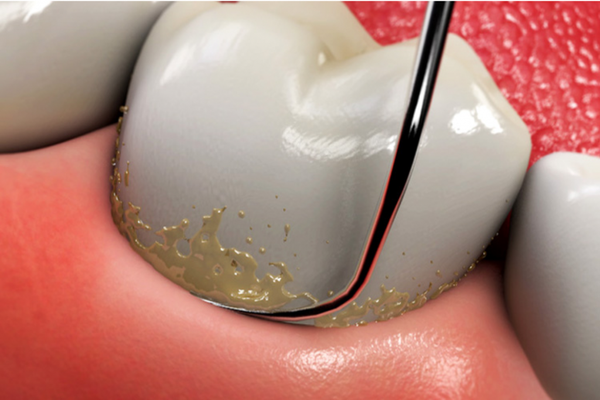

Cao răng tạo thêm diện tích cho mảng bám phát triển, gây ra các bệnh nghiêm trọng như sâu răng và bệnh nướu. Vôi răng không thể tự loại bỏ bằng bàn chải hay bất kỳ dụng cụ nào khác. Việc làm sạch cao răng cần được thực hiện tại phòng khám nha khoa bởi nha sĩ, sử dụng kỹ thuật và máy móc chuyên dụng. Quá trình này gọi là lấy cao răng, thường kết hợp với đánh bóng răng.

Trên thực tế, cạo vôi răng là thủ thuật nha khoa giúp lấy sạch những mảng bám bị vôi hóa trên răng và nướu giúp răng miệng trở nên sạch sẽ và ngăn ngừa các bệnh lý nha khoa nghiêm trọng.

Tuy nhiên, chúng ta không nên lạm dụng việc cạo vôi răng vì điều này sẽ gây tổn thưởng răng của bạn. Hãy cạo vôi răng định kỳ 6 tháng/lần hoặc theo chỉ dẫn của nha sĩ để đạt được hiệu quả tốt nhất.